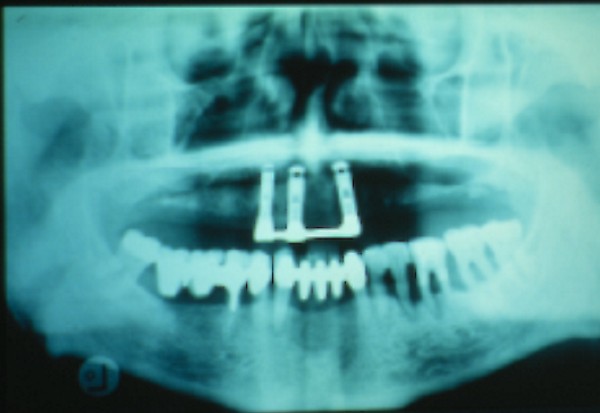

RESUMEN Más allá en el tiempo, respecto de las razones más frecuentes de fracasos como temperatura de fresado, infecciones, falta de fijación inicial, falta de higiene, etc., la OCLUSIÓN recibe sobre sí, la responsabilidad de la permanencia de la osteointegración, como así de la ortofunción del sistema todo. Sometimes ago,conserning the most frecuent reason of failures such as the strawberry action temperature, infections and lack of hygiene…etc.,the OCLUSION has itself the responsability af having the osteointegration well as the allsistem ortofunction . DESARROLLO La valoración de los fracasos en IMPLANTOLOGÍA es difícil de contabilizar sobre todo después del año, ya que el confort logrado por lo general, hace que el paciente realice correctamente sus primeros controles, y después; apoyado en su bienestar; intente subconscientemente olvidar ese período de su vida, que si bien le devolvió su capacidad masticatoria, fonética, social, etc., le ocasionara gastos, molestias, sufrimientos. … la APLICACIÓN de dichas fuerzas, requiere de una exactitud mucho mayor. Los esquemas propuestos a través de los años, no son muchos ni muy variados… I-Evitar las fuerzas tangenciales. II-Repartir las fuerzas lo máximo posible. Sin embargo, muchas veces se confunden los conceptos anteriores con criterios inexactos. Por ej: a-Reducción de las caras vestibulares y palatinas, aceptando que la menor superficie de intercontactos reduce la carga. b-Utilización de la Función de Grupo Posterior, en la creencia de que repartiendo el esfuerzo en las piezas posteriores, ganamos resistencia; a la potencia ejercida por los músculos. c-No permitiendo el contacto excéntrico de un canino implantado, para aliviarlo de las cargas laterales, sobre cargando de esta manera la tabla premolar-molar en el Lado de Trabajo. Algunos conceptos aislados, que forman parte de toda una filosofía de la Oclusión (OCLUSIÓN ORGÁNICA), sean tal vez de ayuda para echar luz sobre los preceptos anteriores. 1º-PROPORCIONES FUNCIONALES DE UN PAR OCLUSAL En la figura siguiente, observamos la relación final masticatoria de un PAR OCLUSAL: En el se ven los contactos puntiformes, producto del choque de superficies redondeadas contra superficies redondeadas («Solo pueden encontrarse en un punto» Ref: Principios Mecánicos Esferoidales.W.Mc.Horris.) Si Miramos con atención este tipo de contactos interoclusales, veremos que la superficie actuante es mucho menor que la superficie total de la cara oclusal: 45% (Fig.1) Por lo tanto, si no es por razones del Pilar de Emergencia para no crear un espacio biológico inadecuado… ¿POR QUÉ REDUCIR LA CARA OCLUSAL VESTÍBULO LINGUALMENTE? (Figs. 2-3-4-5) Si observamos con atención las figuras 2-3-4-5, veremos desde todos los planos , que el área contactante es muy reducida respecto del ancho oclusal total, siendo las fuerzas resultantes , AXIALES al eje implantario. 2º-FUNCIÓN DE GRUPO POSTERIOR. FUNCIÓN CANINA. Tres son las razones por las cuales nos inclinamos a la utilización de la Función Canina. En cambio, en el esquema de FUNCIÓN CANINA, podemos observar que el BRAZO DE POTENCIA, es prácticamente igual al de RESISTENCIA, equilibrando de esta manera la palanca y destruyendo mucho menos las estructuras de soporte(Interface I-H) (Fig. 7) Otra de las razones de peso en este tema es la DIFERENCIA DE ANGULACIÓN que existe entre la cara palatina del canino y las vertientes contactantes del sector premolar-molar. A MAYOR ANGULACIÓN, MENORES FUERZAS LATERALES(Perpendiculares al Plano), y por lo tanto , menor destrucción de la interface Hueso-Implante(Figs. 9-11). DIFERENCIAS EXCITATORIAS DE LOS GRUPOS MUSCULARES. Por último debemos considerar que el intercontacto dentario del sector anterior, estimula excitatoriamente a las fibras anteriores y verticales del temporal (Figs.12-13-14-15), mientras que los contactos posteriores lo hacen con la cincha pterigo-maseterina(Fig. 16-17-18-19) Por lo tanto ,si se comprende el fisiologismo de estos conceptos, es sencillo entender que la sobrecarga de los sectores posteriores es nocivo generando fuerzas tangenciales de Alto Potencial Patológico. 3º-FUNCIÓN DE GRUPO ANTERIOR Las ventajas de un Brazo de Resistencia mayor se acentúan cuando tenemos el esquema de FUNCIÓN DE GRUPO ANTERIOR. Además, debemos tener en cuenta que, durante la función de un Ciclo Masticatorio, es más importante la Desoclusión Final que la Desoclusión Inicial, ya que al ser más larga esta última, es durante el transcurso de su deslizamiento cuando se ejercen fuerzas laterales mayores(Fig. 21) A medida que la punta del canino inferior se acerca a la O.R.C., o sea al Punto de Contacto Intercanino, las fuerzas laterales disminuyen en virtud del acortamiento del brazo de potencia de la palanca, hasta que, al terminar su recorrido, la fuerza es proyectada axialmente sobre el eje del canino superior, debido a que, al margen de la intensidad que la fuerza trae durante el cierre, la dirección de la misma «apunta» en esa dirección. Por eso decimos que los caninos Axializan el Ciclo Masticatorio. Si estamos imitando en lo posible a la naturaleza, no olvidemos este detalle que los dientes naturales provéen, para evitar las fuerzas laterales del canino a la hora de realizar la supraestructura coronaria del mismo. Es ahora menester acentuar que la problemática concreta se manifiesta, no durante la función, sino durante la PARAFUNCIÓN… Cuando estudiamos recorridos de la Dinámica Mandibular, desde el conocido Bicuspoide de Posselt hasta cualquiera de los registros pantográficos, estamos invirtiendo la dirección del movimiento… A.- El primer premolar es el más anterior de la tabla oclusal posterior. Por lo tanto el brazo de resistencia es el mayor de dicha tabla. B.- El lateral, como parte del grupo anterior, cuenta con un empotramiento tipo «clavo largo», y el interseptum lateral -canino, que se opone a la fuerza, es mucho más grueso que la tabla vestibular del primer premolar(Fig.23) C.- Condiciones, las dos anteriores que se favorecen considerablemente, si al enfundar el lateral se logra junto al central una Función de Grupo Anterior. D.- De manera más artificiosa, la instalación de una placa de relajación, soluciona durante la noche lo nocivo de las fuerzas laterales. Veamos un par de casos, como ejemplo de lo dicho: Paciente de 54 años que se presenta a la consulta portando prótesis completa superior y antagonista natural que soporta fundas de porcelana. Obsérvese la función de grupo posterior ejercida, y las consecuencias de la misma: Otro paciente que presenta fractura de la cúspide fundamental de un onlay de porcelana antagonista de cinco piezas implantadas (Fig.27). Radiográficamente se observa la desinserción de uno de sus abuttments cementados (Fig.28). En el Lado de Trabajo (LT), no existe el canino encargado de desocluir la zona afectada (Figs.29-30) Como corolario, cabe entonces una pregunta: ¿Es el Implante en el canino quien debe preservar de patología oclusal al resto del sistema…. ¿Es el Implante…un medio…o un fín? BIBLIOGRAFÍA 1- Dibujos tomados del libro del mismo autor: «OCLUSIÓN ORGÁNICA… UN CAMINO HACIA LA REHABILITACIÓN ORAL»(en preparación) 2- «NEUROFISIOLOGÍA DE LA OCLUSIÓN» 3- «OCLUSIÓN Y FUNCIÓN» 4- «FUNDAMENTOS, TÉCNICAS Y CLÍNICA EN REHABILITACIÓN BUCAL» 5- «OCLUSIÓN Y REHABILITACIÓN» 6- «DISFUNCIÓN TEMPOROMANDIBULAR» 7- «PROCEDIMIENTOS CLÍNICOS Y DE LABORATORIO DE OCLUSIÓN ORGÁNICA» 8- «ESTUDIO ELECTRÓNICO DEL MOVIMIENTO MANDIBULAR» 9- «OCLUSIÓN: CONCEPTO PARA EL CLÍNICO» 10- «IMPLANTOLOGÍA CONTEMPORÁNEA» 11- «OCLUSIÓN Y DIAGNÓSTICO EN REHABILITACIÓN ORAL» 12- «PRINCIPIOS DE OCLUSIÓN»

Erosiones desmedidas a nivel de las piezas posteriores (fig.25), pérdida de un implante distal y el corte necesario del brazo distal de la barra (Fig.26).

Se produce una evidente Función de Grupo Posterior, provocando fuerzas laterales en el Lado de no Trabajo(LnT), siendo estas las INTERFERENCIAS MÁS DELETÉREAS que puede provocar este esquema oclusal, destruyendo las estructuras de ese lado(LnT).